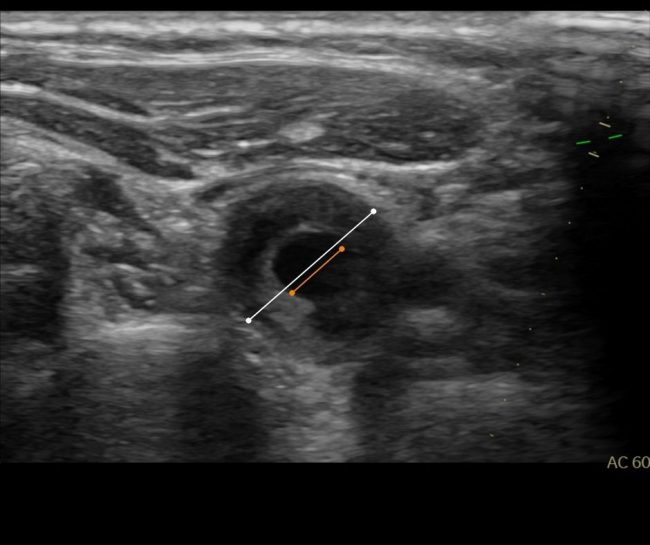

Angiologe Dr. Sven Hausen bietet durch die Ultraschaldiagnostik eine wichtige Methode zur Detektion einer funktionellen Venenschwäche an. Was die Ursachen für so eine Venenschwäche sein kann, lesen Sie im folgenden. Was ist die Funktion von Venenklappen? Venenklappen sind Bestandteil von venösen Gefäßen, um den Rückfluss des Blutes entgegen der Schwerkraft zu verhindern. Die meisten Venenklappen…